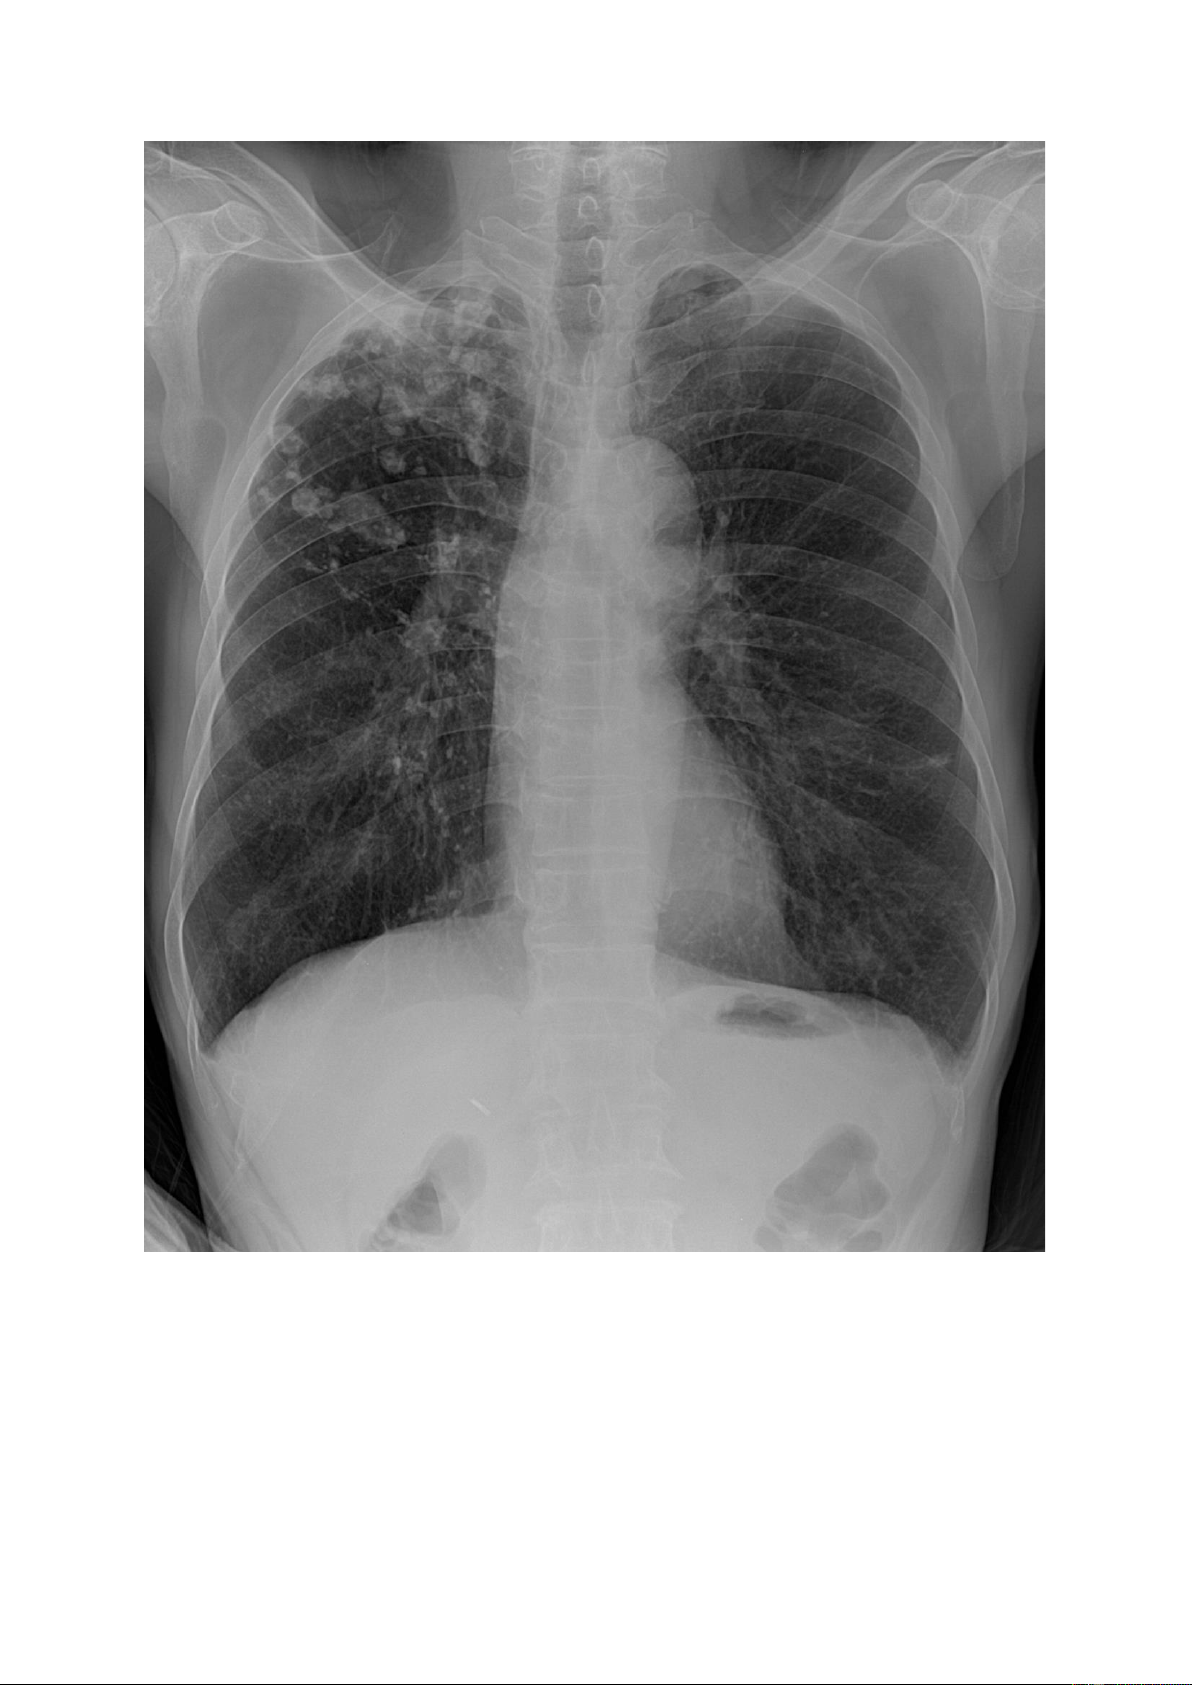

Đám mờ: là tổn thương có sự tập trung của các nốt mờ theo vùng tạo thành

hình ảnh vùng mờ không đồng đều, không rõ bờ của vùng tổn thương đó. lOMoAR cPSD| 22014077 1.5.